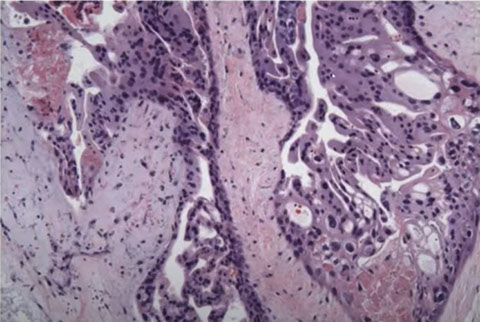

Micro: Diffuse, circumferential trophoblastic prolif of uniformly enlarged, avascular edematous villi c marked prolif or trophoblasts that can be atypical

- early complete moles have uniform pop of villi that are big for gestational age, and villous edema c central cistern formation may not be present

- trophoblastic proliferation may also be focal or less developed in early dz

- villi have primitive appearance c inc mesenchymal cellularity and karyorrhexis and necrobiosis (not seen in partial mole or hydropic abortus)

Characteristic findings in CHM with cavitation and absence of fetal vessels. Note the contents completely degenerating and filled with protein rich fluid on the left.

CHM. Trophoblast hyperplasia which is exuberant and circumferential

Early CHM. Looks like toes on a foot with deep clefting. Note the blue myxoid stroma. Pitfall: Can be found in early gestations.

PHM. Intermixed biphasic population of villi by size. Proposed stringent threshold for villous enlargement >2.5 mm

PHMs have complex, irregular shapes in larger villi

PHMs have inclusions that reflect the shape complexity

Micro: mix of edematous and normal villi

- villous scalloping (irregular shape with trophoblast villi goes into villous stroma)

- do not develop uniformly hydropic villi, giving it a biphasic population of hydropic villi mixed c smaller fibrotic immature villi

- have stromal trophoblastic pseudoinclusions

- circumferential trophoblast proliferation less pronounced than in complete moles